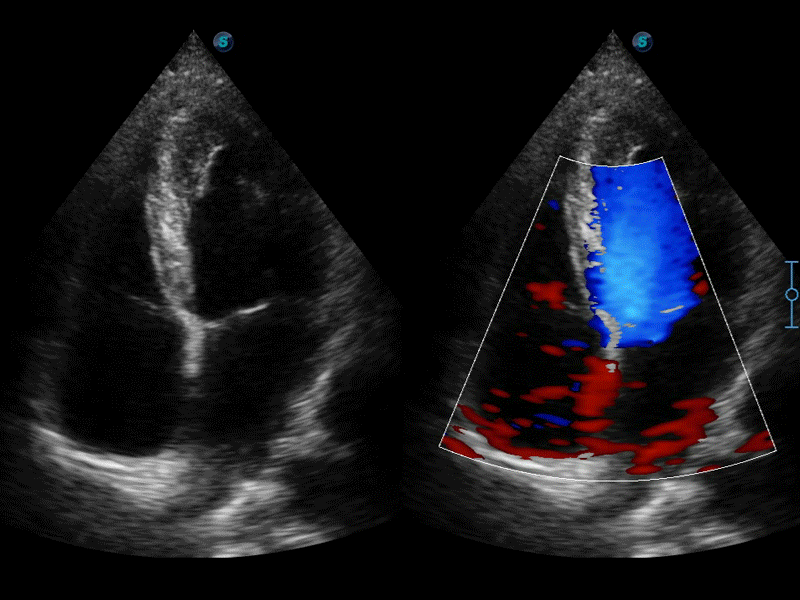

自動(dòng)識(shí)別收縮和舒張末期心肌內(nèi)膜,自動(dòng)計(jì)算射血分?jǐn)?shù)EF值。